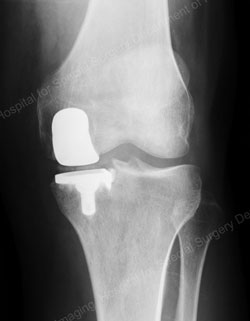

Figure: A valgus stress view shows an intact lateral compartment in a good candidate for a unicondylar knee replacement